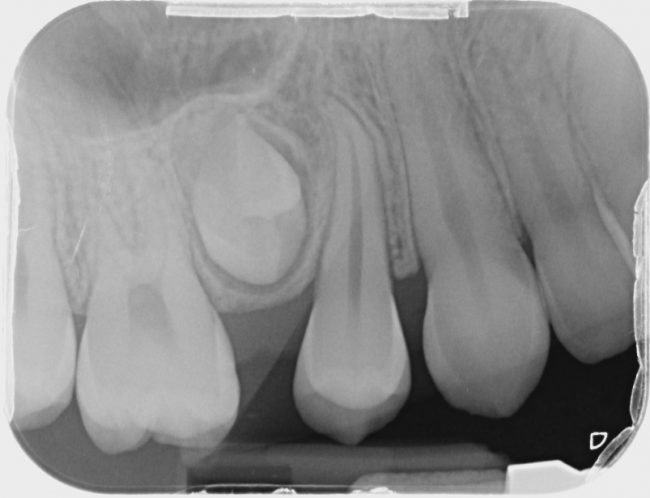

Un caso di anomalia di formazione radicolare

Diverse sono le anomalie che incontriamo nel nostro percorso lavorativo, ma la mancata formazione della radice di un elemento dentale, è cosa abbastanza inaspettata. In questa breve presentazione voglio condividere la mia scelta terapeutica per essere di aiuto a chi si dovesse trovare nella mia stessa situazione e per stimolare ulteriori proposte terapeutiche. Voi come…